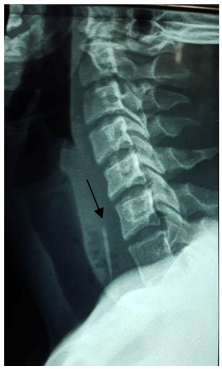

Case 1: A 40-year-old man, with no previous medical history, consulted for high dysphagia, a fever. The notion of fish bone ingestion, evolving for 5days was found. Clinical examination revealed an inflammation on the posterior wall of the oropharynx. A cervical x-ray and a CT-Scan showed the foreign body (Figure 1). Endoscopy did not found the foreign body Surgical exploration (Figure 2) allowed the drainage of the abscess, and extraction of the fish bone. Parenteral antibiotic was administrated. After 45days, patient was reviewed without particularity.

Figure 1 A cervical x-ray and a CT-Scan showed the foreign body betwen jugular vein and carotid.